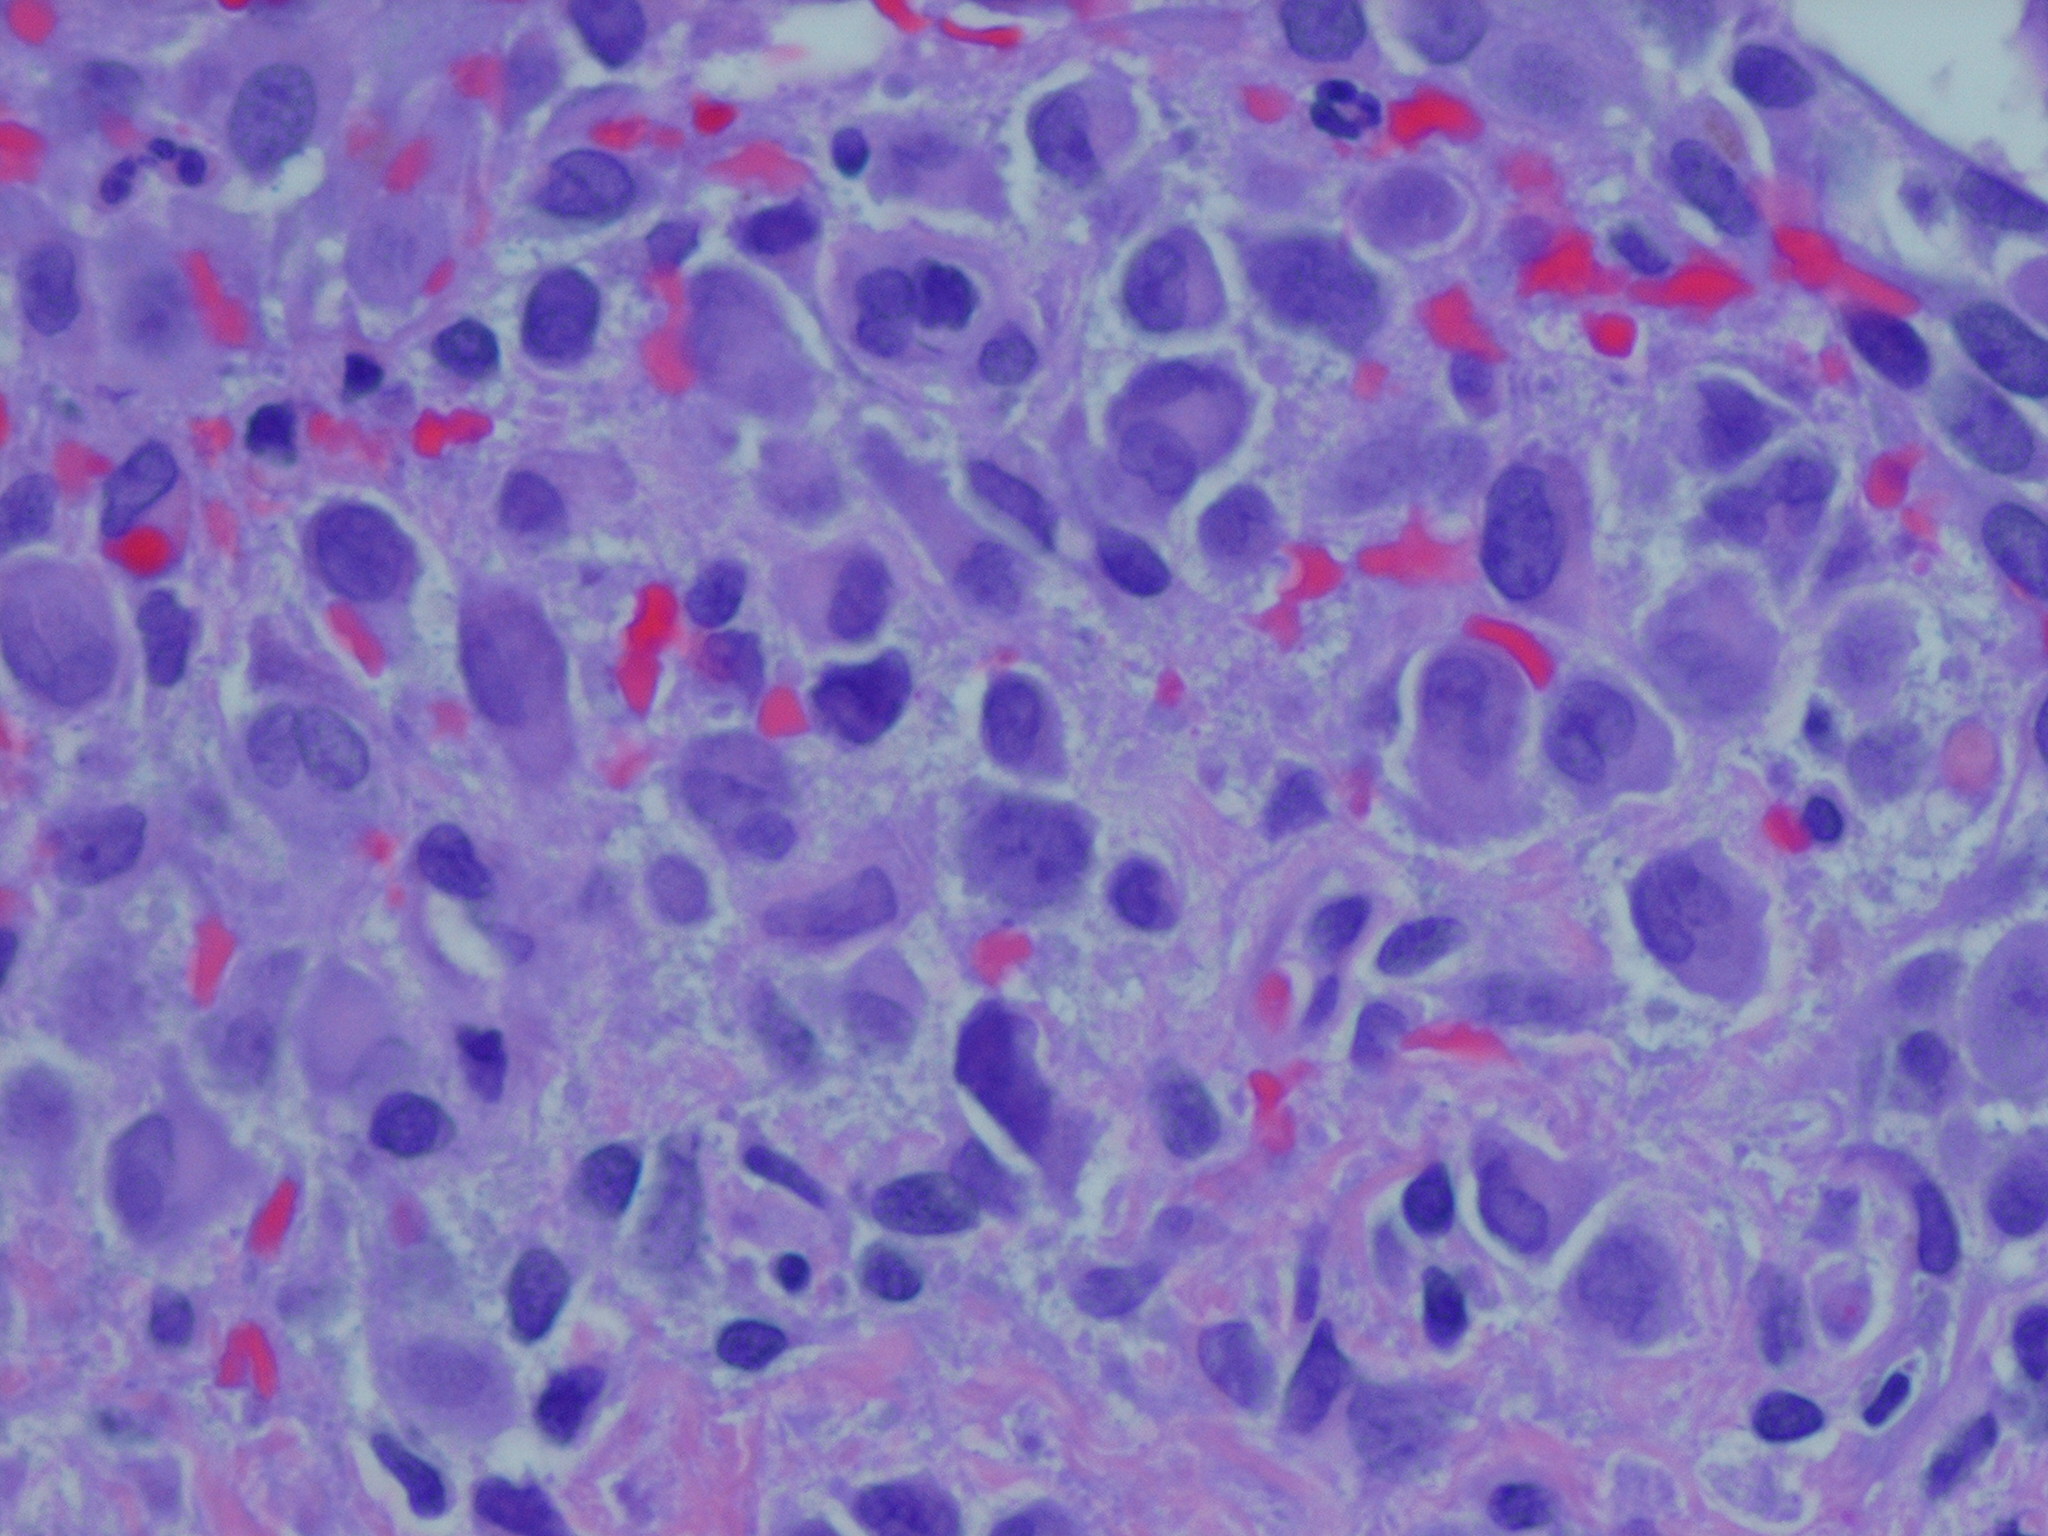

Langerhans cell histiocytosis = كثرة الخلايا الناسجة لانغرهانس